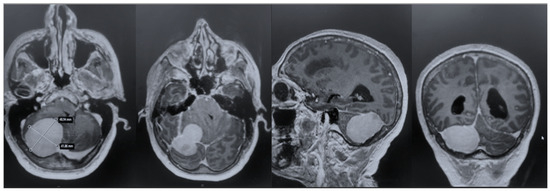

After admission, the patient underwent a cerebral MRI, which showed a huge extra-axial lesion in the posterior cranial fossa (5 × 4.4 × 4.3 cm). The lesion demonstrated low SI on T1 and intermediate SI on T2 and avidly enhancing post-Gad administration. The mass showed no restriction on DWI. The mass was broad-based on the right tentorium cerebelli with a discrete supratentorial extension, compressing the adjacent right cerebellar hemisphere, the cerebellar peduncle, the brainstem, the IV ventricle, and the right occipital lobe. A characteristic dural tail sign was demonstrated on post-Gad sequences (Figure 1).

To strengthen the oncologic perspective, we added an 18-month contrast-enhanced MRI, demonstrating no residual or enhancing recurrence (Figure 5). While early postoperative findings were favorable, meningiomas require longer-term surveillance. Our current imaging aligns with standard practice and supports durable tumor control at 1 year. Continued surveillance will follow institutional protocol, with annual MRI for at least 5 years, tailored to WHO grade, Simpson resection grade, and histopathology.

Figure 1. Preoperative MRI + C: a posterior fossa extra-axial mass was demonstrated, showing a low SI on T1 and intermediate SI on T2, which avidly enhanced post-Gad administration. The mass was broad-based on the right tentorium cerebelli with a discrete supratentorial extension, thus compressing the adjacent right cerebellar hemisphere, the brainstem, the IV ventricle, and the right occipital lobe.

Figure 5. Post-contrast T1-weighted MRI at 18 months following resection. Axial and sagittal images at the level of the prior tumor demonstrate no nodular or mass-like enhancement to suggest residual or recurrent meningioma.